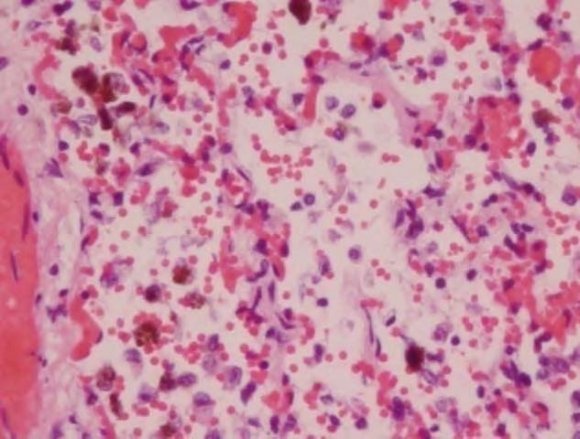

In addition, all members of the family had reduced RBC hemoglobin (Hb) and were diagnosed as anemic. Nose bleeds and a flu-like illness were other common symptoms (Table 1). After moving out of the contaminated home, their health improved, however, they remained symptomatic with the RADS/asthma as well as other symptoms such as fatigue and generally not feeling as well as they did prior to occupation. There was no family history of von Willebrand disease. The following abnormalities were listed in the final autopsy report: (1) liver had mold congestion; (2) Heart had mild hypertrophy without inflammation; (3) Lungs had marked vascular congestion, foci peribronchial inflammation, intra-alveolar blood numerous aggregates of pigment laden macrophages (hemosiderosis) (Figure 1). All other organs were normal in appearance.. The cause of death was listed as respiratory failure with pulmonary bleeding and hemosiderosis.

The entire family had episodes of nose bleeds. However, the conditions of the twins were more serious leading to hospital stays. It is noteworthy that Stachylysin has been detected in the sera of mice, humans and indoor environment of water damaged homes and buildings (46). In addition, several species of Aspergillus and Penicillium are known to produce hemolysins and probably siderophores (21,22,(47)(48)(49). Thus, both nasal and pulmonary bleeding may well have been the result of multiple mold hemolysins as well as infection from mold and bacteria. The female twin recovered sufficiently but developed RADS. The fraternal brother was found dead in his crib with bleeding from his nose and mouth. The autopsy revealed pulmonary bleeding and hemosiderosis (Fig. 1).

Histology of the Lung (H & E)